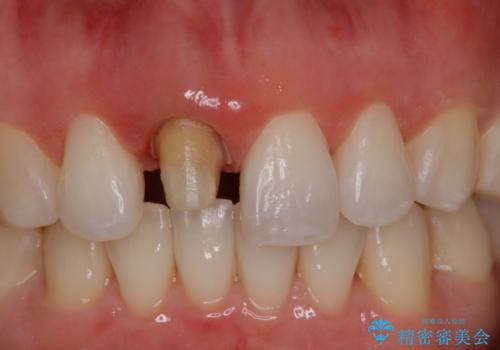

矯正の時使用していた仮歯を新調し、その後最終的な形を作ってから型取りを行います。

- 仮歯で矯正治療を行い、治療終了したためセラミックにて最後仕上がりをきれいにされたいという患者様の症例です。